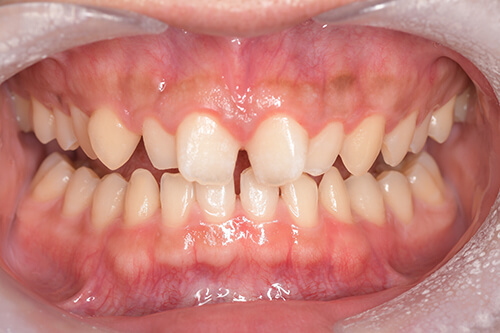

CASE 2

| 年齢・性別 | 30代・男性 |

|---|---|

| 主訴 | 歯石を取りたい |

| 治療内容 | 超音波スケーラーでの歯石除去 |

| 治療期間 | 60分 |

| 治療費 | 初診料を含め約4,500円 |

| リスク・副作用 | 歯ぐきに違和感や痛みを覚える場合がある。 1週間程度、歯を磨くといつもより出血することがある。 腫れていた歯ぐきが引き締まることで歯ぐきが下がった様に見える。 歯ぐきが下がることで歯がみしやすくなることがある。 一時的に歯の動揺(ゆれ)が増す場合がある。 |